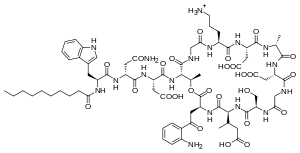

Biosynthesis

Daptomycin is a cyclic lipopeptide antibiotic produced by Streptomyces roseosporus.[30][31] Daptomycin consists of 13 amino acids, 10 of which are arranged in a cyclic fashion, and three on an exocyclic tail. Two nonproteinogenic amino acids exist in the drug, the unusual amino acid L-kynurenine (Kyn), only known to daptomycin, and L-3-methylglutamic acid (mGlu). The N-terminus of the exocyclic tryptophan residue is coupled to decanoic acid, a medium-chain (C10) fatty acid. Biosynthesis is initiated by the coupling of decanoic acid to the N-terminal tryptophan, followed by the coupling of the remaining amino acids by nonribosomal peptide synthetase (NRPS) mechanisms. Finally, a cyclization event occurs, which is catalyzed by a thioesterase enzyme, and subsequent release of the lipopeptide is granted.

The NRPS responsible for the synthesis of daptomycin is encoded by three overlapping genes, dptA, dptBC and dptD. The dptE and dptF genes, immediately upstream of dptA, are likely to be involved in the initiation of daptomycin biosynthesis by coupling decanoic acid to the N-terminal Trp.[32] These novel genes (dptE, dptF ) correspond to products that most likely work in conjunction with a unique condensation domain to acylate the first amino acid (tryptophan). These and other novel genes (dptI, dptJ) are believed to be involved in supplying the nonproteinogenic amino acids L-3-methylglutamic acid and Kyn; they are located next to the NRPS genes.[32]

The decanoic acid portion of daptomycin is synthesized by fatty acid synthase machinery (Figure 2). Post-translational modification of the apo-acyl carrier protein (ACP, thiolation, or T domain) by a phosphopantetheinyltransferase (PPTase) enzyme catalyzes the transfer of a flexible phosphopantetheine arm from coenzyme A to a conserved serine in the ACP domain through a phosphodiester linkage. The holo-ACP can provide a thiol on which the substrate and acyl chains are covalently bound during chain elongations. The two core catalytic domains are an acyltransferase (AT) and a ketosynthase (KS). The AT acts upon a malonyl-CoA substrate and transfers an acyl group to the thiol of the ACP domain. This net transthiolation is an energy-neutral step. Next, the acyl-S-ACP gets transthiolated to a conserved cysteine on the KS; the KS decarboxylates the downstream malonyl-S-ACP and forms a β-ketoacyl-S-ACP. This serves as the substrate for the next cycle of elongation. Before the next cycle begins, however, the β-keto group undergoes reduction to the corresponding alcohol catalyzed by a ketoreductase domain, followed by dehydration to the olefin catalyzed by a dehydratase domain, and finally reduction to the methylene catalyzed by an enoylreductase domain. Each KS catalytic cycle results in the net addition of two carbons. After three more iterations of elongation, a thioesterase enzyme catalyzes the hydrolysis, and thus release, of the free C-10 fatty acid.

To synthesize the peptide portion of daptomycin, the mechanism of an NRPS is employed. The biosynthetic machinery of an NRPS system is composed of multimodular enzymatic assembly lines that contain one module for each amino acid monomer incorporated.[33] Within each module are catalytic domains that carry out the elongation of the growing peptidyl chain. The growing peptide is covalently tethered to a thiolation domain; here it is termed the peptidyl carrier protein, as it carries the growing peptide from one catalytic domain to the next. Again, the apo-T domain must be primed to the holo-T domain by a PPTase, attaching a flexible phosphopantetheine arm to a conserved serine residue. An adenylation domain selects the amino acid monomer to be incorporated and activates the carboxylate with ATP to make the aminoacyl-AMP. Next, the A domain installs an aminoacyl group on the thiolate of the adjacent T domain. The condensation (C) domain catalyzes the peptide bond forming reaction, which elicits chain elongation. It joins an upstream peptidyl-S-T to the downstream aminoacyl-S-T (Figure 7). Chain elongation by one aminoacyl residue and chain translocation to the next T domain occurs in concert. The order of these domains is C-A-T. In some instances, an epimerization domain is necessary in those modules where L-amino acid monomers are to be incorporated and epimerized to D-amino acids. The domain organization in such modules is C-A-T-E.[33]

The first module has a three-domain C-A-T organization; these often occur in assembly lines that make N-acylated peptides.[33] The first C domain catalyzes N-acylation of the initiating amino acid (tryptophan) while it is installed on T. An adenylating enzyme (Ad) catalyzes the condensation of decanoic acid and the N-terminal tryptophan, which incorporates decanoic acid into the growing peptide (Figure 3). The genes responsible for this coupling event are dptE and dptF, which are located upstream of dptA, the first gene of the Daptomycin NRPS biosynthetic gene cluster. Once the coupling of decanoic acid to the N-terminal tryptophan residue occurs, the condensation of amino acids begins, catalyzed by the NRPS.

The first five modules of the NRPS are encoded by the dptA gene and catalyze the condensation of L-tryptophan, D-asparagine, L-aspartate, L-threonine, and glycine, respectively (Figure 4). Modules 6-11, which catalyze the condensation of L-ornithine, L-aspartate, D-alanine, L-aspartate, glycine, and D-serine are encoded for the dptBC gene (Figure 5). dptD catalyzes the incorporation of two nonproteinogenic amino acids, L-3-methylglutamic acid (mGlu) and Kyn, which is only known thus far to daptomycin, into the growing peptide (Figure 6).[31] Elongation by these NRPS modules ultimately leads to macrocyclization and release in which an α-amino group, namely threonine, acts as an internal nucleophile during cyclization to yield the 10-amino-acid ring (Figure 6). The termination module in the NRPS assembly line has a C-A-T-TE organization. The thioesterase domain catalyzes chain termination and release of the mature lipopeptide.[33]

The molecular engineering of daptomycin, the only marketed acidic lipopeptide antibiotic to date (Figure 8), has seen many advances since its inception into clinical medicine in 2003.[34] It is an attractive target for combinatorial biosynthesis for many reasons: second generation derivatives are currently in the clinic for development;[35] Streptomyces roseosporus, the producer organism of daptomycin, is amenable to genetic manipulation;[36] the daptomycin biosynthetic gene cluster has been cloned, sequenced, and expressed in S. lividans;[35] the lipopeptide biosynthetic machinery has the potential to be interrupted by variations of natural precursors, as well as precursor-directed biosynthesis, gene deletion, genetic exchange, and module exchange;[36] the molecular engineering tools have been developed to facilitate the expression of the three individual NRPS genes from three different sites in the chromosome, using ermEp* for expression of two genes from ectopic loci;[37] other lipopeptide gene clusters, both related and unrelated to daptomycin, have been cloned and sequenced,[29] thus providing genes and modules to allow the generation of hybrid molecules;[36] derivatives can be afforded via chemoenzymatic synthesis;[38] and lastly, efforts in medicinal chemistry are able to further modify these products of molecular engineering.[35]

New derivatives of daptomycin (Figure 9) were originally generated by exchanging the third NRPS subunit (dptD) with the terminal subunits from the A54145 (Factor B1) or calcium-dependent antibiotic pathways to create molecules containing Trp13, Ile13, or Val13.[39] dptD is responsible for incorporating the penultimate amino acid, 3-methyl-glutamic acid (3mGlu12), and the last amino acid, Kyn13, into the chain. This exchange was achieved without engineering the interpeptide docking sites. These whole-subunit exchanges have been coupled with the deletion of the Glu12-methyltransferase gene, with module exchanges at intradomain linker sites at Ala8 and Ser11, and with variations of natural fatty-acid side chains to generate over 70 novel lipopeptides in significant quantities; most of these resultant lipopeptides have potent antibacterial activities.[29][39] Some of these compounds have in vitro antibacterial activities analogous to daptomycin. Further, one displayed ameliorated activity against an E. coli imp mutant that was defective in its ability to assemble its inherent lipopolysaccharide. A number of these compounds were produced in yields that spanned from 100 to 250 mg/liter; this, of course, opens up the possibility for successful scale-ups by fermentation techniques. Only a small percentage of the possible combinations of amino acids within the peptide core have been investigated thus far.[40]